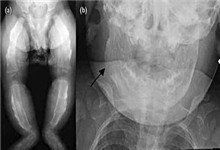

X線表現 先為輕度骨皮質增厚,以後逐漸出現明顯的骨膜下新骨形成。全身骨骼隊指及趾外,均可受累,最常見為下頜骨,其次順序為肋骨、鎖骨、尺骨、橈骨、肩胛骨、脛骨及腓骨,長骨病變最明顯的部位是骨幹,而骨骺及乾骺端常不受侵犯,骨彎曲,肢體增長。在個別病例,新骨形成過多時,可致誤診為惡性腫瘤。大多數病人在數月後可自愈,不留任何痕跡,但在少數人可遺留輕微的病變痕跡及肢體過長。